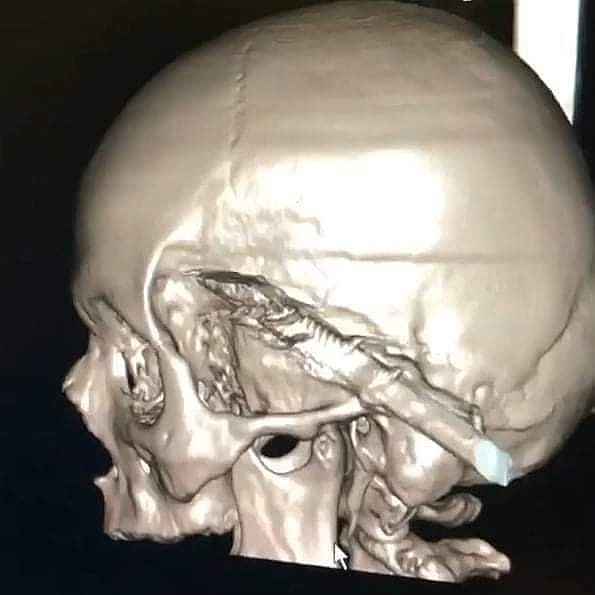

Kastamonu'da uyuduğu sırada koltuktan düşen yaşlı şahsın başına soba maşası saplandı. Maşanın bir kısmı itfaiye ekiplerince kesilirken, kalan kısım ise ameliyatla alındı.

Edinilen bilgiye göre, Araç ilçesinde ikamet eden ve ismi öğrenilemeyen yaşlı şahıs, koltukta uyuduğu sırada düşmesi sonucu kafasına soba maşası saplandı. İhbar üzerine yaralanan yaşlı şahıs, 112 Acil Sağlık ekiplerince Araç Devlet Hastanesine kaldırıldı. Burada ilk müdahalesi yapılan yaşlı şahıs, ardından Kastamonu Devlet Hastanesine sevk edildi. Burada tedavi altına alınan yaşlı şahsın kafasına saplanan soba maşasının bir kısmı, ilk olarak itfaiye ekiplerince kesildi. Ardından kafa tasında kalan kısım ise, yapılan ameliyat ile çıkarıldı. Kafasından soba maşası çıkarılan yaş şahıs, daha sonra servise alınarak tedavisine başlandı.

Edinilen bilgiye göre, Araç ilçesinde ikamet eden ve ismi öğrenilemeyen yaşlı şahıs, koltukta uyuduğu sırada düşmesi sonucu kafasına soba maşası saplandı. İhbar üzerine yaralanan yaşlı şahıs, 112 Acil Sağlık ekiplerince Araç Devlet Hastanesine kaldırıldı. Burada ilk müdahalesi yapılan yaşlı şahıs, ardından Kastamonu Devlet Hastanesine sevk edildi. Burada tedavi altına alınan yaşlı şahsın kafasına saplanan soba maşasının bir kısmı, ilk olarak itfaiye ekiplerince kesildi. Ardından kafa tasında kalan kısım ise, yapılan ameliyat ile çıkarıldı. Kafasından soba maşası çıkarılan yaş şahıs, daha sonra servise alınarak tedavisine başlandı.